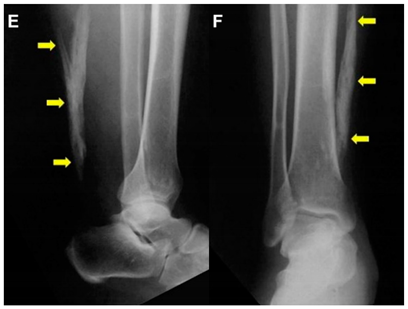

| Akhaddar, 2014 c [7] | A 52-year-old man. This image submission included plain radiographs with a lateral and an antero-posterior view of the right leg and ankle. Arrows indicate a 10-cm ossification of the Achilles Tendon without a fracture (Images E and F). The patient presented after acute trauma to the foot, and the ossified mass was an incidental finding. The patient had no symptoms of the lower leg at presentation and had no history of metabolic or systemic illness nor ankle trauma. Surgery was not performed due to the lack of symptoms. | ![]() |